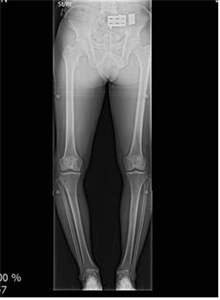

[°­µ¿±¸ ´Þ·Á¶óº´¿ø ÀåÁ¾ÈÆ ¿øÀåÀÇ ÀÇÇлó½Ä] ¹«¸­ °üÀý¿°À¸·Î À̾îÁö´Â ÈØ´Ù¸®, Ä¡·á Çʼö

¹«¸­ °üÀý¿°À¸·Î À̾îÁö´Â ÈØ´Ù¸®, Ä¡·á Çʼö "ȯÀںР³ªÀ̰¡ 45¼¼µµ ¾ÈµÇ¾ú´Âµ¥, ¹«¸­Àº 70´ë ¹«¸­À̱º¿ä. ÀÌ ³ªÀÌ¿¡ Àΰø°üÀý ¼ö¼úÀ» ÇÒ ¼öµµ ¾ø°í Å«ÀÏ...